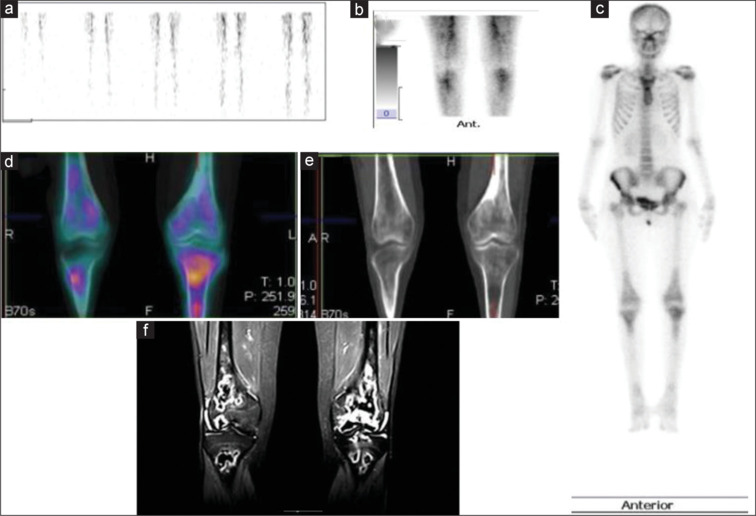

目的:骨显像是一种评价疑似骨坏死患者的灵敏成像方法。我们评估了骨单光子发射计算机断层扫描/计算机断层扫描(SPECT/CT) (CBS)对已知风湿病或其他结缔组织疾病和临床怀疑骨坏死患者的诊断性能,并与磁共振成像(MRI)进行了比较。方法:这项前瞻性诊断准确性研究纳入了70例临床怀疑骨坏死的患者,他们接受了平面三期骨扫描以及区域SPECT/CT (CBS)和区域MRI。MRI被认为是诊断CBS的敏感性、特异性、预测值和准确性的标准。科恩的kappa统计也计算了协议。结果:根据疑似骨坏死的关节部位分布:髋关节21例,膝关节43例,踝关节6例。70例患者中有30例MRI检出骨坏死。CBS的敏感性为100%(检测到30/70),特异性为97%(假阳性2/40)。总的来说,两次扫描对于骨坏死的诊断有很好的一致性(Cohen’s kappa统计值= 0.94)。除了可疑部位外,CBS在13例患者的19个其他无症状部位检测到骨坏死。结论:本研究表明,包括全身成像和SPECT/CT在内的CBS在检测骨坏死方面具有高度敏感性,其准确性与局部MRI相当。其固有的全身成像技术可以检测多灶性骨坏死。它可以作为常规x线平片后的早期检查方式来确定诊断。

Results: The distribution of the patients based on the joint regions suspected to have osteonecrosis is as follows: 21 hip, 43 knee, and six ankle. MRI detected osteonecrosis in 30/70 patients. CBS had a sensitivity of 100% (30/70 were detected) and a specificity of 97% (2/40 were false positive). Overall, there was good agreement between the two scans regarding the diagnosis of osteonecrosis (Cohen's kappa statistic = 0.94). In addition to the suspected sites, CBS detected osteonecrosis in 19 additional asymptomatic sites in 13 patients.